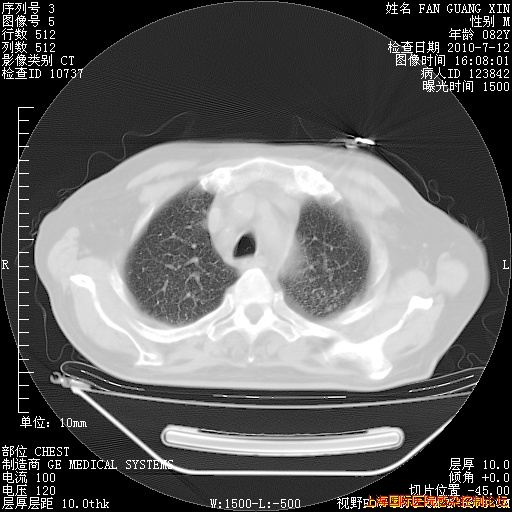

补发6月12日肺部CT肺窗

6月12日肺窗

整整相隔30天的肺部CT好像有所好转啊。甲强龙减量第3天,需要观察体温。

海管,自昨日你和我通完话后,不知您岳父消化道症状有无缓解?体温怎样?阅读7.12日胸部ct,个人认为目前激素治疗是有效的,甲强龙减量是适宜的。因在抗痨治疗,需密切观察肝功、肾功能和血常规。不过,老年、长期住院和大量使用激素,很担心菌群失调发生